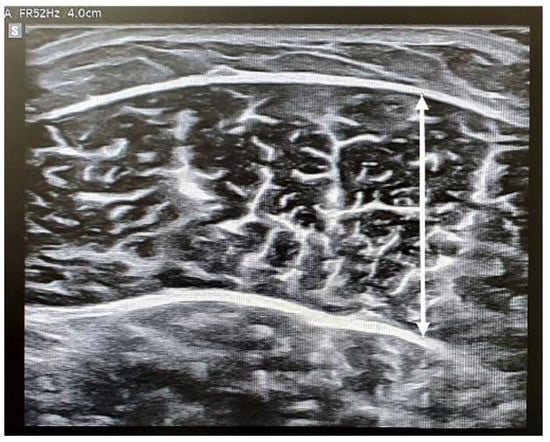

Bモード(2次元超音波画像表示)を用いて断面で測定した。その後、プローブを筋繊維の方向に回転させ、SWEモードを使用して縦断面の静止筋硬度および収縮筋硬度を取得した。筋厚は、表層部と深層部の腱膜の距離として測定した。

筋スティフネスについては、円形の関心領域は直径5mmで、筋線維に平行に配置。局所的な貫通欠損や線維性隔壁は避けた。各 SWE 画像に 4 つの関心領域の円を作成し、剛性値の平均を算出した。値はPkaで記録された。筋厚と剛性は同じ位置から取得した。